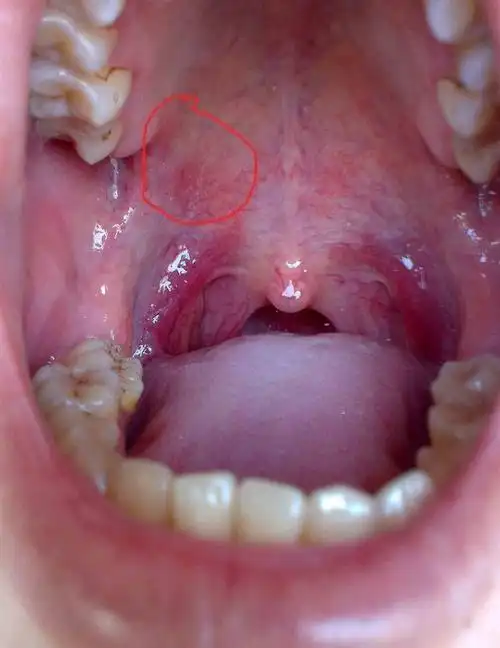

口腔黏膜局灶性上皮增生

我在口腔右边长了一个痘痘是怎么回事不痛不痒不知道什么时候长的刚刚

口腔上颚长个硬疙瘩大概一个月左右之前是上颚干疼特别是晚

口腔里长了个小白点,在小舌头旁边,靠近喉咙的地方,有点类似于粉刺的

请问口腔上面长了个肉豆,像脸上很大的豆豆一样,注:本人经常长口腔

嘴里长了个肉芽一样的东西 是什么啊 用舌头碰只有

口腔里肿痛明显红肿起来咀嚼吞咽东西时